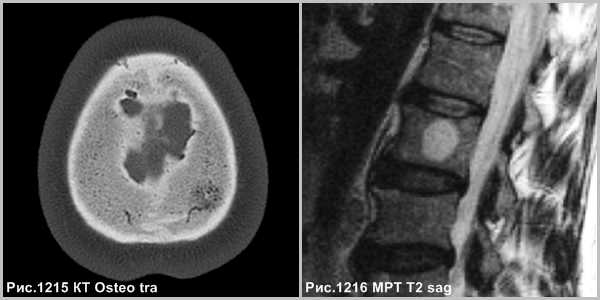

Очаговое изменение в диплоическом веществе свода черепа (рис.1215) и очаг в толще губчатого вещества тела позвоночника (рис.1216), состоящее из кавернозных полостей.

Морфологически различают первичную внутрикостную гемангиому и гемангиомы мягких тканей, вторично поражающих кости черепа (гемангиоматоз). Первичные внутрикостные гемангиомы растут медленно, как правило, расположены в губчатой кости. В большинстве они доброкачественные, но редко могут быть локально агрессивными. На КТ определяется рассасывание губчатого вещества с наличием радиальных костных балок. Гемангиома медленно растет (5-6лет), иногда самопроизвольно прекращает рост, сопровождаясь жировой инволюцией.

Гемангиома в плоских костях черепа - не частое образование, которое располагается преимущественно в диплоическом слое. Имеется разряженное строение губчатого вещества и толстые костные трабекулы, радиально расходящиеся в стороны. Очаг разряжения губчатого вещества в толще диплоического слоя определяется как зона↓плотности на КТ (стрелка на рис.1221) и↑МР-сигнала на Т2 и Flair (головки стрелок на рис.1219-1221).

Крупная гемангиома в теле L5 позвонка, распространяющаяся на всё его тело, приводящая к перестройке губчатого вещества кости, с разряжением губчатого вещества и наличием вертикальных утолщенных костных балок (головки стрелок на рис.1222,1223). Гемангиома в теле позвонка, имеющая жировую интенсивность МР-сигнала - ↑сигнал по Т1, с обозначением контура на последовательности в противофазе (головка стрелки на рис.1224), и имеющая выпадение МР-сигнала в режиме Т2 с жироподавлением (стрелка на рис.1224), что соответствует жировой ткани в гемангиоме.